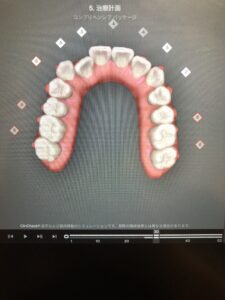

私のもともとの歯並びがこちらです。